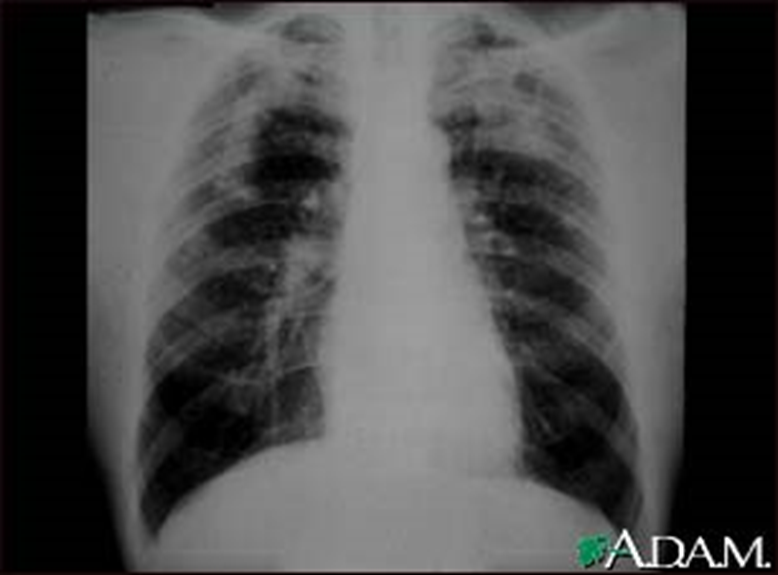

(2)X线胸片表现:煤工尘肺X线胸片也是其病理改变在胸片上的反映,煤工尘肺不论是矽肺还是煤肺,X线上主要表现为圆形小阴影、不规则形小阴影和大阴影,还可见到肺纹理和肺门阴影的异常改变。

1)圆形小阴影:煤工尘肺X线表现以圆形小阴影为主者多见,多为p或q型阴影,其病理基础是矽结节、煤矽结节和煤尘纤维灶。圆形小阴影的形态、数量和大小往往与患者接触粉尘的性质和浓度有关。纯掘进工患者可为典型矽肺表现;以掘进作业为主,接触含游离二氧化硅较多的混合性粉尘工人,以典型的小阴影居多;以采煤作业为主的工人,主要接触煤尘,并混有少量矽尘所患尘肺胸片上圆形小阴影多不太典型,边缘不整齐,呈星芒状,密集度低。圆形小阴影最早出现在右中肺区,其次为左中、右下肺区,左下及两上肺区出现的较晚。随着病变的进展,小阴影逐渐增多、增大、密集度增高,分布范围扩展,可布满全肺。

2)不规则形小阴影:较圆形小阴影响少见。多呈网状,有的密集成蜂窝状,致密度不高。其病理基础为煤尘灶、弥慢性肺间质纤维化、细支气管扩张、肺小叶中心性肺气肿。

3)大阴影:是晚期矽肺和煤矽肺的重要X线表现,呈椭圆形、长梭形或不规则形,边缘清晰,周边肺气肿明显。大阴影多是由小阴影增大、密集、融合而形成;也可由少量斑片、条索状阴影逐渐相连并融合呈条带状。周边肺气肿比较明显,形成边缘清楚、密度较浓、均匀一致的大阴影。多在两肺上、中区出现,左右对称。煤肺患者晚期罕见大阴影。

complicated coal workers pneumoconiosis complicated coal workers pneumoconiosis

此外,煤工尘肺的肺气肿多为弥慢性、局限性和泡性肺气肿。泡性肺气肿表现为成堆小泡状阴影,直径为1~5mm,即所谓“白圈黑点”。晚期可见肺大泡。

此外,煤工尘肺可见到肺纹理增多、增粗、扭曲变形,肺门阴影增大、密度增高,还可见到淋巴结蛋壳样钙化或桑椹样钙化阴影,胸膜增厚、钙化改变者较少见,但常可见到肋膈角闭锁及粘连。